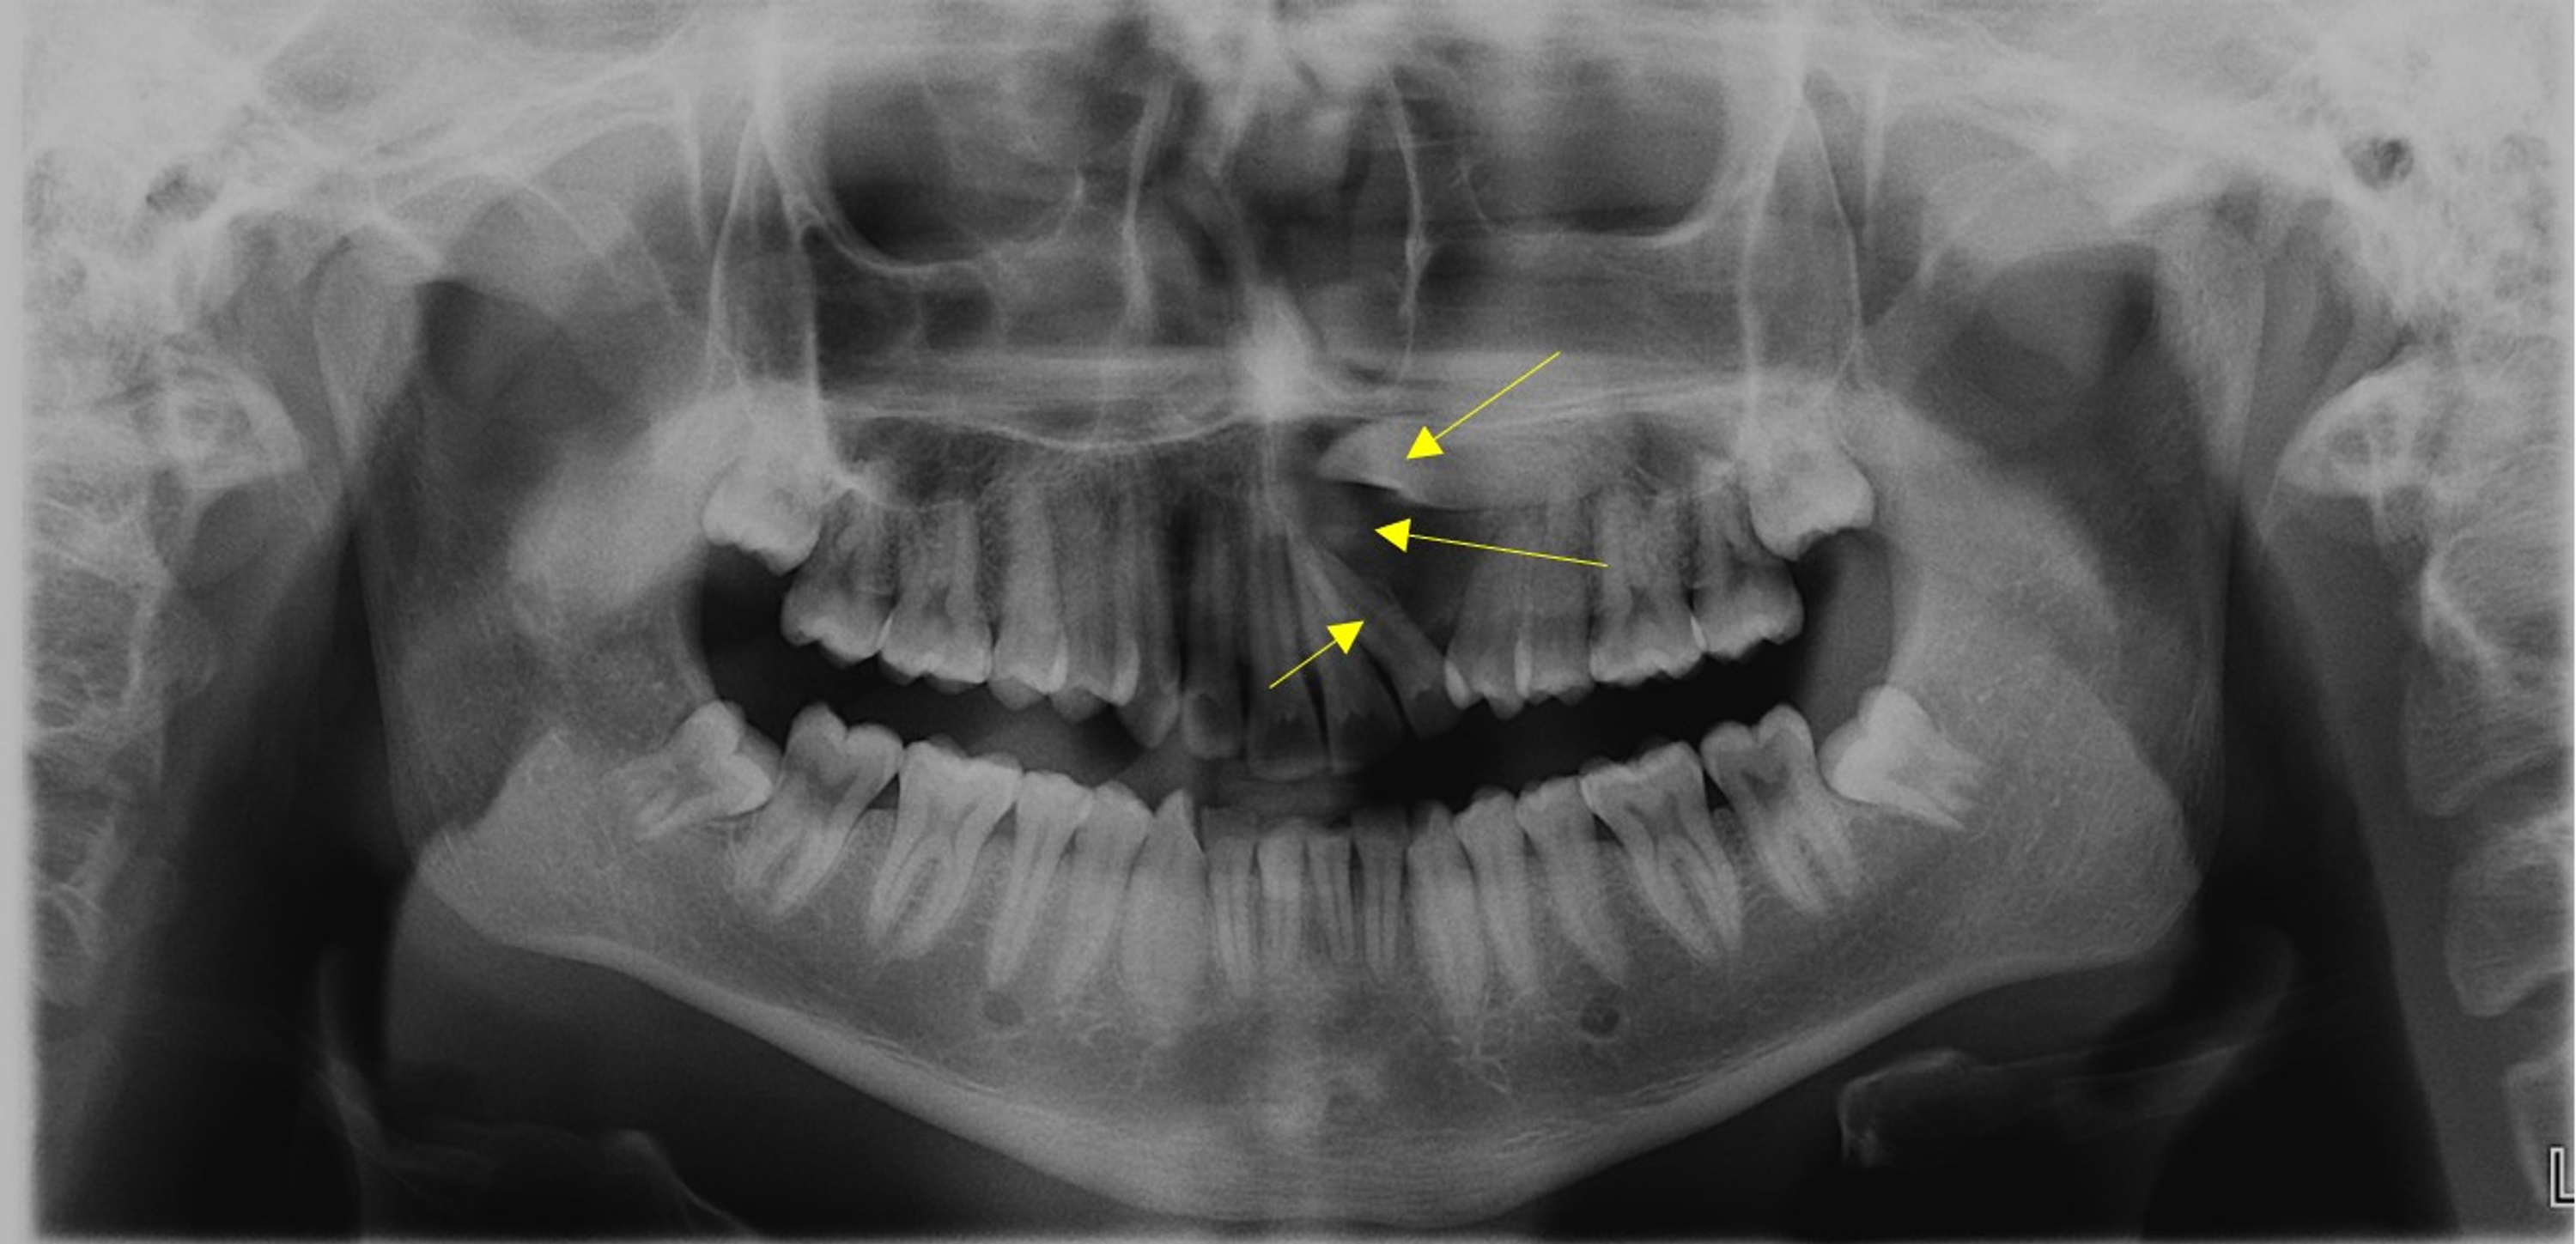

Maxillary Odontogenic Keratocyst . — the odontogenic keratocyst (okc) is one of the most aggressive odontogenic cysts. odontogenic keratocysts (okc), previously known as keratocystic odontogenic tumors (kcot or kot), are rare benign cystic lesions involving the mandible or. The main difference between okcs and other jaw cysts. — an odontogenic keratocyst (okc) is a benign but aggressive intraosseous tumor derived from the. — odontogenic keratocysts (okcs), first described by philipsen in 1956 [1], are benign intraosseous lesions of. figure 5 odontogenic keratocyst between roots of right maxillary incisors (circled by white dots). — odontogenic keratocysts (okc), previously known as keratocystic odontogenic tumours (kcot or kot), are. — the odontogenic keratocyst (okc) is one of the most aggressive odontogenic cysts.

— odontogenic keratocysts (okcs), first described by philipsen in 1956 [1], are benign intraosseous lesions of. figure 5 odontogenic keratocyst between roots of right maxillary incisors (circled by white dots). The main difference between okcs and other jaw cysts. — an odontogenic keratocyst (okc) is a benign but aggressive intraosseous tumor derived from the. odontogenic keratocysts (okc), previously known as keratocystic odontogenic tumors (kcot or kot), are rare benign cystic lesions involving the mandible or. — the odontogenic keratocyst (okc) is one of the most aggressive odontogenic cysts. — odontogenic keratocysts (okc), previously known as keratocystic odontogenic tumours (kcot or kot), are. — the odontogenic keratocyst (okc) is one of the most aggressive odontogenic cysts.

Maxillary Odontogenic Keratocyst The main difference between okcs and other jaw cysts. — an odontogenic keratocyst (okc) is a benign but aggressive intraosseous tumor derived from the. The main difference between okcs and other jaw cysts. — odontogenic keratocysts (okc), previously known as keratocystic odontogenic tumours (kcot or kot), are. — the odontogenic keratocyst (okc) is one of the most aggressive odontogenic cysts. — the odontogenic keratocyst (okc) is one of the most aggressive odontogenic cysts. — odontogenic keratocysts (okcs), first described by philipsen in 1956 [1], are benign intraosseous lesions of. odontogenic keratocysts (okc), previously known as keratocystic odontogenic tumors (kcot or kot), are rare benign cystic lesions involving the mandible or. figure 5 odontogenic keratocyst between roots of right maxillary incisors (circled by white dots).